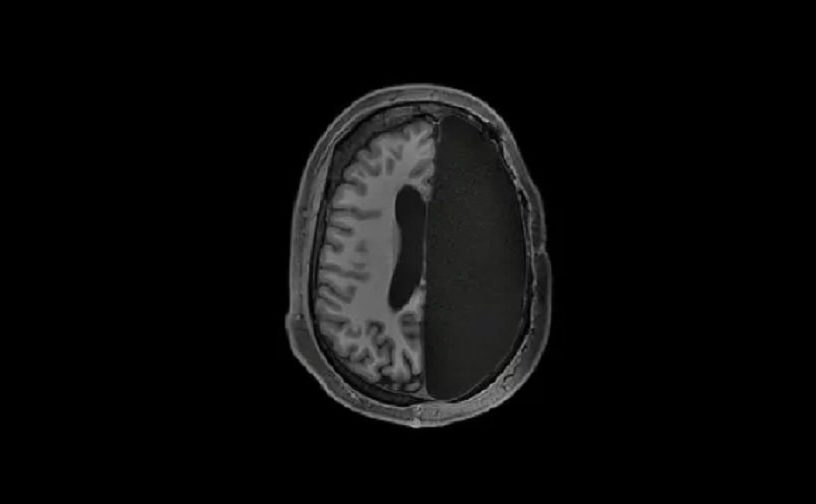

Dans certaines pathologies neurologiques, comme l’épilepsie chronique, le traitement le plus adapté consiste en l’ablation de l’hémisphère cérébral défectueux. Une telle opération est appelée « hémisphérectomie » et est dans la majorité des cas pratiquée durant l’enfance (entre 5 mois et 15 ans). Mais comment ces personnes vivent-elles ensuite avec une moitié...